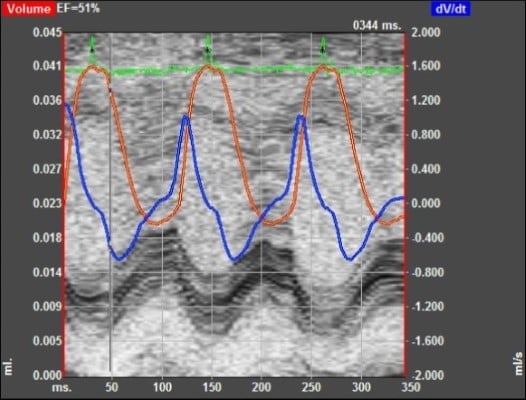

- VisualSonics Vivo 2100 imaging System cardiac echo

Normal Day-0 Preoperative Baseline Echo Data

Day-14 Post operative Chronic MI